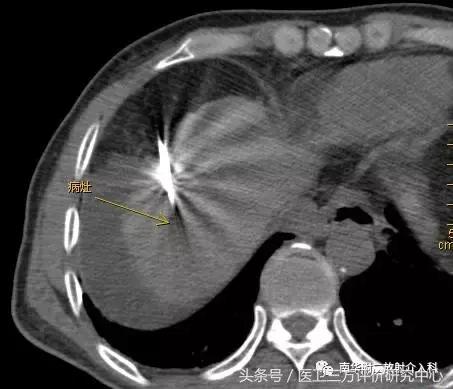

CT引导精准定位

患者曹某,男,63岁,有乙肝肝硬化,近3月来血AFP持续增高,我院CT及MRI增强扫描示肝SⅧ段占位,拟诊小肝癌,跟病人及家属商议后决定行微波消融治疗;遂于昨日下午在CT引导、局部+静脉联合麻醉下顺利完成了微波消融术治疗。手术时间约45分钟,术后患者未诉特殊不适,现恢复良好,已可下床自由行走。在此特别感谢麻醉科、消化内科及介入室老师的鼎力支持!